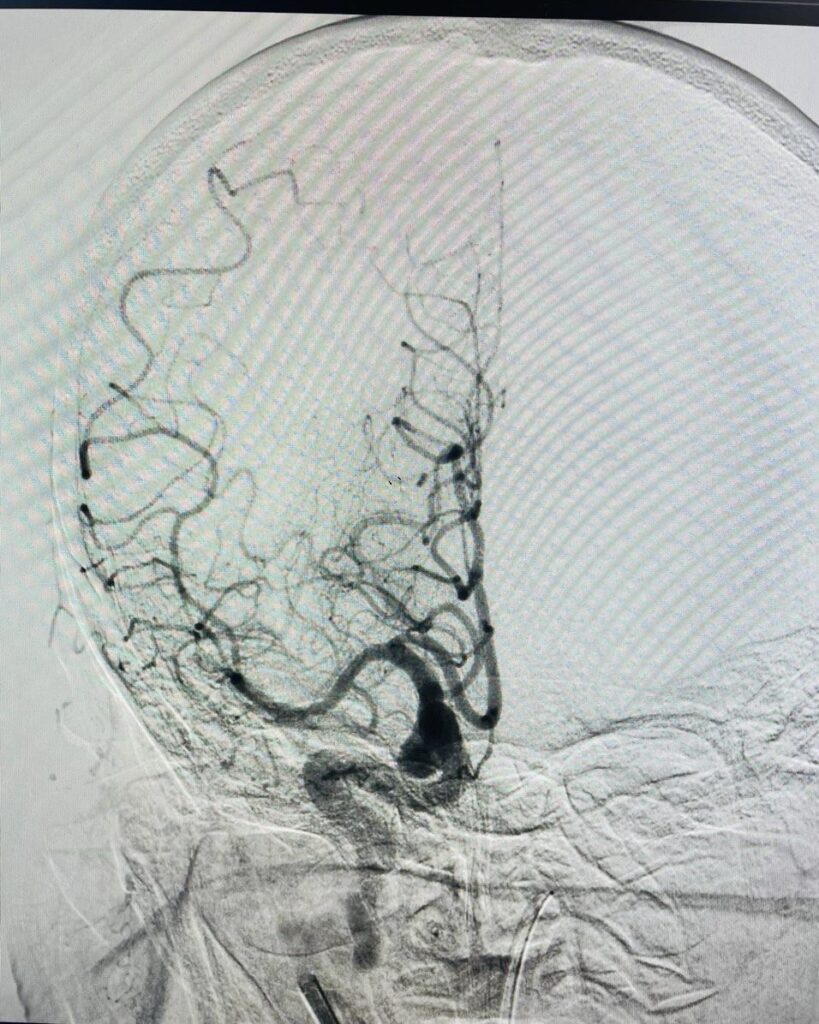

Що таке церебральна ангіографія

Церебральна ангіографія – це процедура, яка дає змогу перевірити наявність аномалій, звужень та бляшок у кровоносних судинах головного мозку методом рентгенологічного дослідження судин головного мозку та шиї.

Як виконують церебральну ангіографію

Перед початком процедури Вам буде встановлено катетер у вену (на руці або передпліччі) для введення седативного препарату. Однак, деяким пацієнтам може знадобитися загальна анестезія.

Ваша голова утримуватиметься на місці за допомогою ременя, щоб ви не могли завадити процедурі рухами головою під час процедури. Ваш лікар знеболить ділянку шкіри за допомогою місцевого анестетика.

Лікар зробить дуже маленький надріз у ділянці зап’ястя (рідше – в паховій ділянці). Під рентгенівським контролем катетер (довга тонка порожниста пластикова трубка) вводиться в кровоносну судину через крихітний отвір, зроблений голкою.

Потім через катетер вводять контрастну речовину. Коли контрастна речовина досягне кровоносних судин, буде зроблено кілька серій рентгенівських знімків. Коли процедуру буде завершено, лікар видалить катетер і накладе тиснучу пов’язку. Процедура зазвичай триває протягом 1-2 годин.